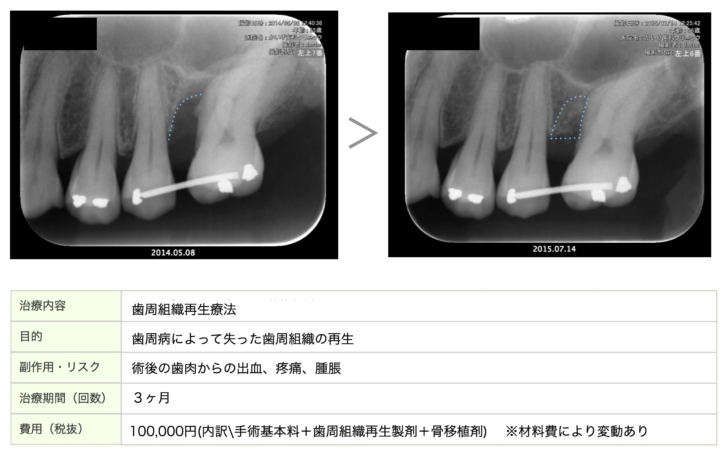

歯周組織再生療法(再生療法)とは?

しかしながら、歯周病治療の中で歯周外科手術と呼ばれる治療方法があり、

その中でも、歯周組織再生療法と呼ばれる失った骨を再生させる方法もございます。

当院では、歯周病治療に真摯に取り組み10年以上の歯周病治療の再生療法の実績がございます。

下記に10年前に行った再生療法の症例をご紹介します。

失った骨の形態や噛み合わせなどにより、全ての患者様に再生療法が適応できる訳ではないですが、現在では症例や材料により保険適応ができる症例もございます。